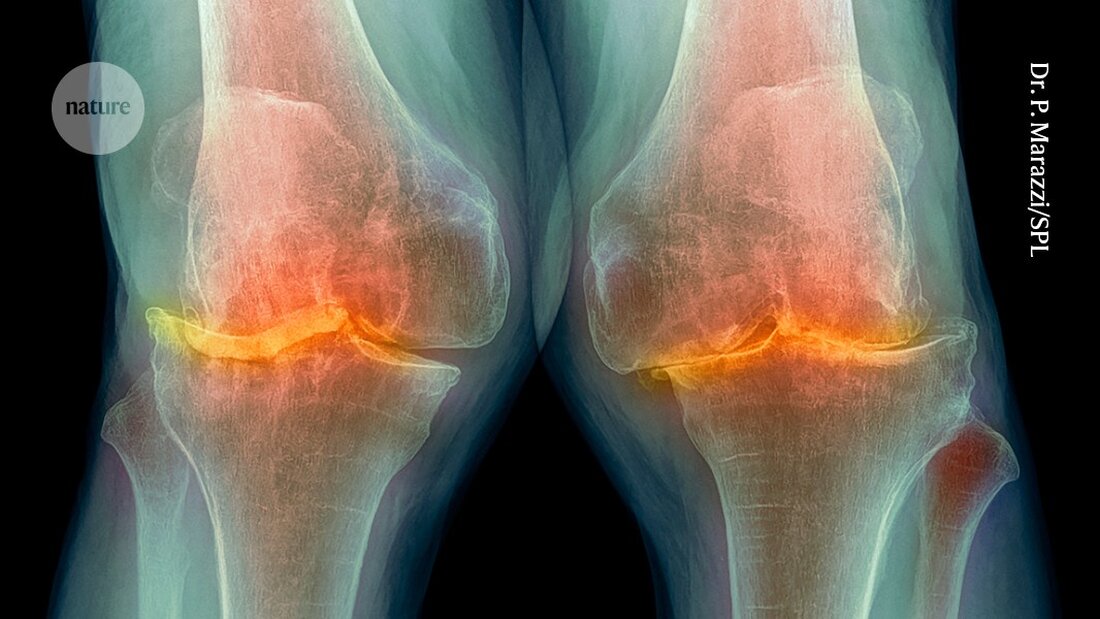

Ein Wundermittel zur Gewichtsreduktion reduziert erheblich Schmerzen bei adipös bedingter Kniearthrose und verbessert die Fähigkeit einer Person, Aktivitäten wie das Gehen auszuführen. Dies belegt eine klinische Studie, die in 11 Ländern durchgeführt wurde – die erste ihrer Art, die nachweist, dass eines von der neuen Generation von Anti-Adipositas-Medikamenten auch zur Behandlung von Arthritis eingesetzt werden kann. Das Medikament Semaglutid hat eine Schmerzreduktion erzielt, die mit der von Opioidmedikamenten vergleichbar ist.

Verbreitende Plage

Osteoarthritis, die zu steifen und schmerzhaften Gelenken führt, gehört zu den häufigsten Alterskrankheiten, wobei das Kniegelenk am häufigsten betroffen ist. Menschen mit Adipositas haben ein erhöhtes Risiko, an Kniearthrose zu erkranken, weil zusätzliches Gewicht eine höhere Belastung für die Gelenke bedeutet. Callahan berichtet, dass Adipositas auch die Symptome verschlechtert. Schmerzen durch diese Erkrankung können Menschen daran hindern, sich zu bewegen, was es extrem schwierig macht, Gewicht durch Änderungen des Lebensstils zu verlieren, sagt Bliddal.

Diese Verbesserung könnte teilweise auf die verringerte Belastung des Knies durch den Gewichtsverlust zurückzuführen sein, schreiben die Autoren. Aber Semaglutid hat auch entzündungshemmende Wirkungen, die möglicherweise zur Schmerzlinderung beitragen.